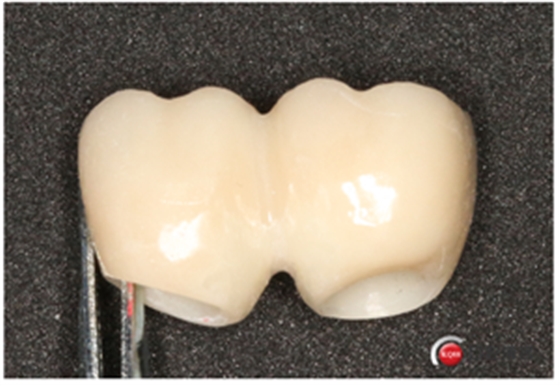

試戴冠,看起來還不錯哈,但我不滿意,大家看看有什么問題?看看下頜那幾顆比較明顯。

問題在這里,不給留位置怎么會有齦乳頭,沒有間隙怎么清潔?這完全是技工的錯吧?算了我自己修整一下吧。

再看看是不是效果好多了?哼!我就是個較真兒的人。